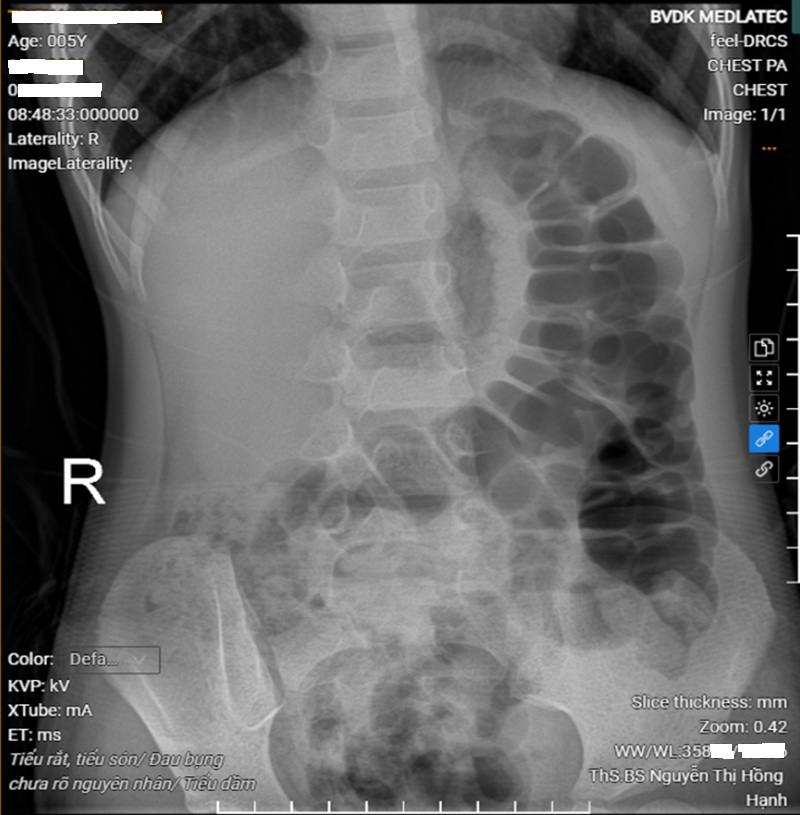

Kết quả xét nghiệm cho thấy, các chỉ số máu trong giới hạn bình thường, không có dấu hiệu nhiễm trùng; xét nghiệm nước tiểu bình thường, loại trừ nhiễm khuẩn đường tiết niệu. Siêu âm ổ bụng hiện tại chưa thấy có bất thường của đường tiết niệu. Hình ảnh X-quang ổ bụng, ghi nhận nhiều quai đại tràng giãn, chứa hơi và phân, gợi ý tình trạng ứ phân đại tràng do táo bón chức năng.

Hình ảnh chụp X-quang ổ bụng của bệnh nhi thấy nhiều quai đại tràng giãn, chứa hơi và phân

Từ các kết quả đó, bác sĩ nghĩ nhiều đến tình trạng táo bón, ứ phân kéo dài có thể chèn ép bàng quang, làm giảm dung tích chứa nước tiểu và gây rối loạn phản xạ tiểu tiện, dẫn đến tiểu dầm, tiểu rắt và tiểu són kéo dài ở trẻ nhỏ.